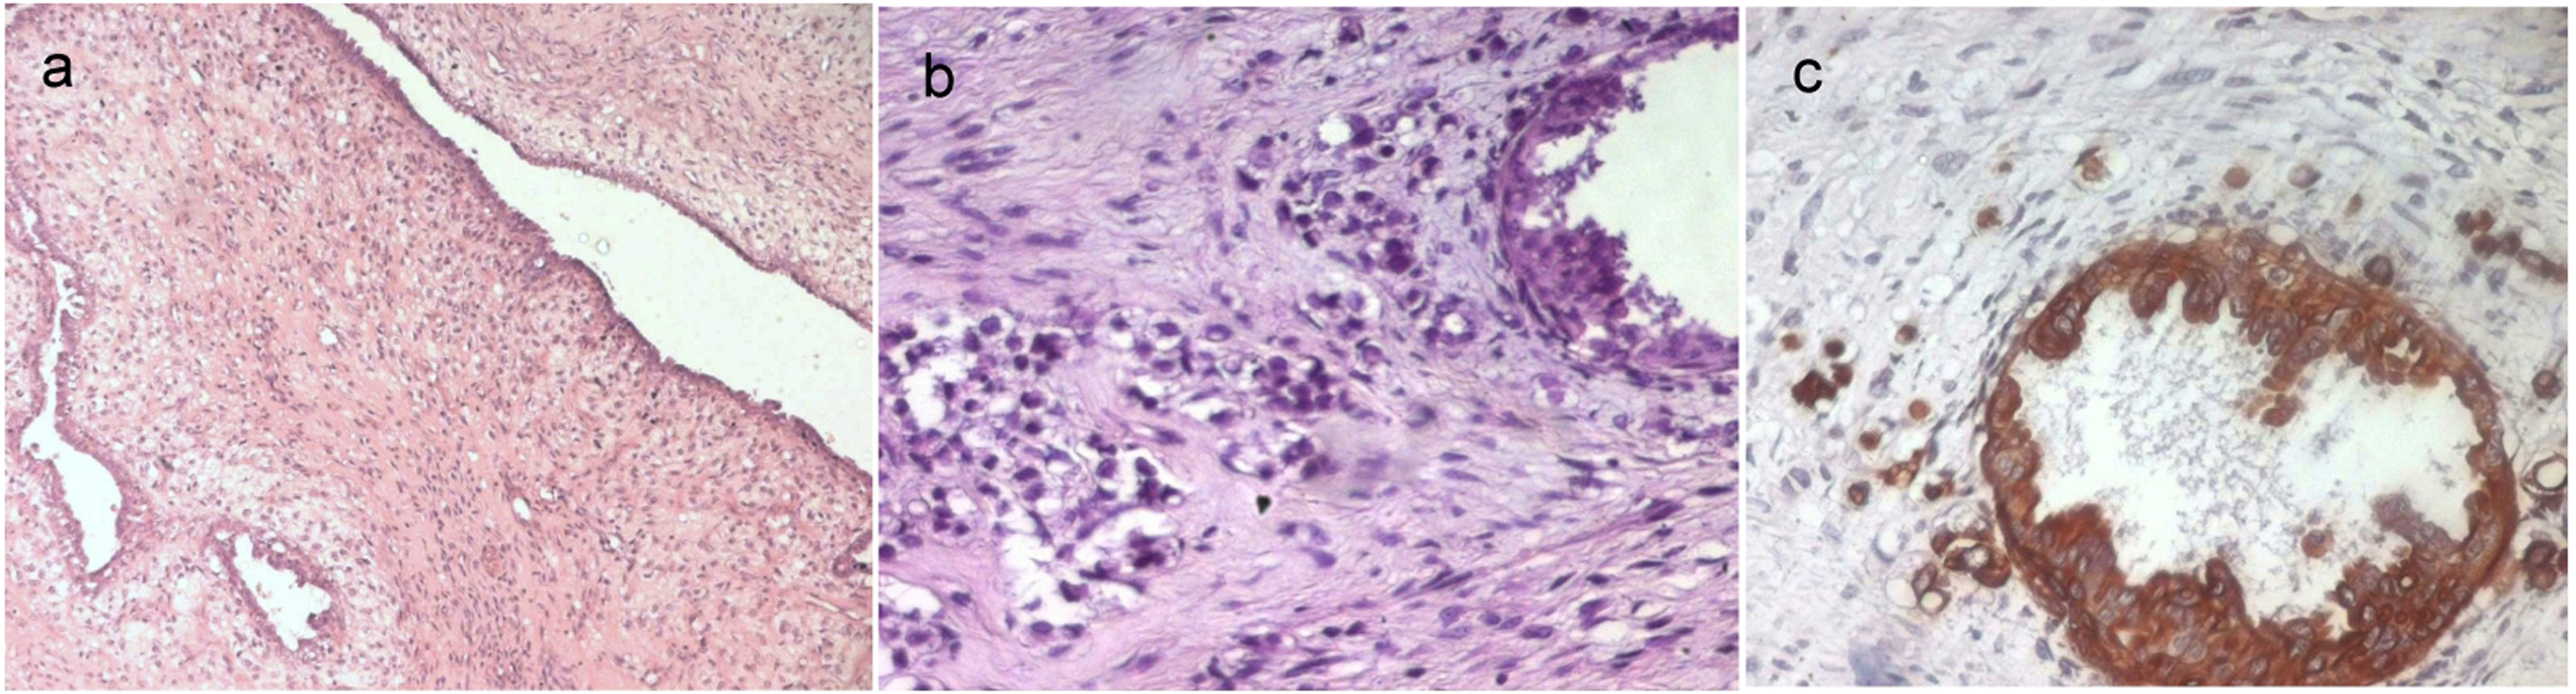

These features were consistent with the diagnosis of a borderline phyllodes tumor (Fig. 1a). The epithelial component of this tumor showed foci of ductal carcinoma in situ with a massive and cribriform pattern and foci of invasive mammary carcinoma (Fig. 1b). The ductal carcinoma in situ was of an intermediate nuclear grade. The invasive carcinoma was of no special type, Scarff-Bloom-Richardson (SBR) grade II. There were no oestrogen or progesterone receptors in either the stromal or the epithelial elements. Immunohistochemical stain showed immunoreactivity for Epithelial Membrane Antigen and cytokeratin in the epithelial component (Fig. 1c), while spindle cells were completely negative for these markers.

![]() Click for large image | Figure 1. a: A borderline phyllodes tumor (HE x 50); b: The epithelial component of the phyllodes tumor showed foci of in situ and invasive ductal carcinoma (HE x 400); c: Immunoreactivity for cytokeratin of the intraductal and invasive carcinoma (IHC x 400). |